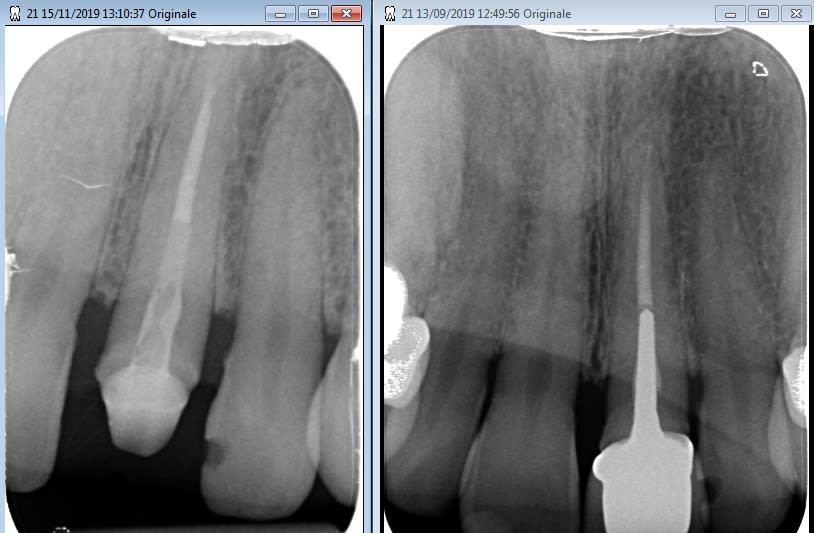

Petit sondage du matin: sur une radio similaire, céramique à reprendre pour raisons esthétiques, traitement endo correct et asymptomatique:

Qui dépose l'IC?

Quels sont vos critères décisionnels?

Ah ben c'était une richmond, du coup...